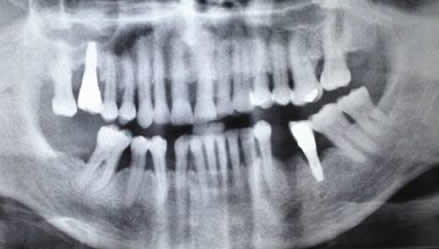

La proyección panorámica u ortopantomografía, es la modalidad mas usada en el estudio preoperatorio de los implantes dentales. (10). Es simple y barata, pero proporciona información insuficiente. Genera distorsión geométrica en el 25% de los casos, por la superposición de estructuras. (2, 7, 10). (Fig 20 C).

Fig 20 C. Ortopantomografía normal

Ausencia de varias piezas dentales. También hay implantes colocados, en el lado derecho del maxilar y el izquierdo de la mandíbula.